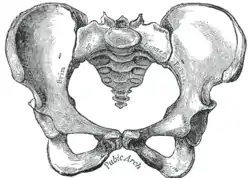

![]() Жіночий таз | |

Статеві відмінності

Істотною відмінністю сучасних людей є двоногість і збільшений об'єм мозку. Оскільки розмір таза тісно пов'язаний з ними (досить велика голова плода має проходити через малий таз), природний відбір опинився перед двома суперечливими вимогами: достатня ширина пологового каналу й водночас вузькість для ефективності при прямоходінні; цей конфлікт відомий як «акушерська дилема». Жіночий таз («гінекоїдний таз»)[6] еволюціонував до своєї максимальної ширини, необхідної для дітонародження: ширший просто зробив би жінку нездатною для ходьби. І навпаки, чоловічий таз не мав потреби адаптуватися для пологів, тому розвивався в бік найоптимальнішої ширини для двоногого пересування[7].

Основні відмінності між чоловічим і жіночим малим і великим тазами включають:

- Жіночий таз є об'ємнішим і ширшим за чоловічий, який є більш високим, вузьким і компактним[8].

- Жіноча верхня апертура малого таза ширша і має овальну форму, тоді як у чоловіків у неї виступає мис крижової кістки, тож форма апертури має радше серцеподібну форму[8].

- Стінки чоловічого таза сходяться у напрямку від входу в малий таз до виходу з нього, а стінки жіночого навпаки розходяться[9].

- Кут між нижніми гілками лобкових кісток (підлобковий кут) у чоловіків є гострим (70°), а в жінок тупим (90–100°)[8]. Окрім того, кістки лобкової дуги в жінок більш увігнуті, у чоловіків пряміші[10].

- Відстань між сідничними кістками є невеликою в чоловіків, що робить вихід з малого таза вузьким, але значна в жінок, що утворює відносно широкий вихід. Ості і горби сідничних кісток у чоловіків є масивнішими й вдаються сильніше в тазову порожнину. Велика сіднична вирізка в жінок ширша[10].

- Гребені клубових кісток у чоловіків сильніше виражені і вище розташовані, що робить чоловічий великий таз глибшим і вужчим за жіночий[10].

- Чоловічі крижі довгі, вузькі, пряміші, і мають виражений мис. Жіночі крижі коротші, ширші, більш вигнуті дозаду, крижовий мис виражений слабкіше[10].

- Кульшова западина ширша в жінок, ніж у чоловіків[10]. Чоловіча кульшова западина спрямована латеральніше, жіноча же — фронтальніше. Отже, при ходьбі нога чоловіка може рухатися взад і вперед тільки в одній площині. У жінок же нога мусить повертатися вперед і всередину, а головка стегна відводить її назад в іншій площині. Це зумовлює особливості жіночої ходи (наприклад, хитання кульшами)[11].